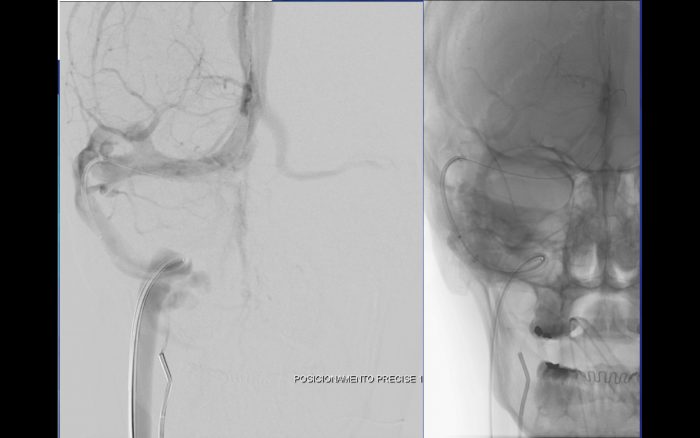

O caso ilustrado é de uma paciente de 33 anos com papiledema, cefaleia intensa, zumbido e perda progressiva do campo visual. Foram realizadas aferioções da pressão em todo trajeto do seio transverso e sigmoide direito, sendo evidenciado diferença de pressão de 10 mm/Hg relacionada ao ponto de estenose. Após o diagnóstico, foi instituído o tratamento por angioplastia com Stent (Precise – Cordis), devido sua facilidade de navegação e acomodação em tortuosidades. O procedimento transcorreu sem intercorrências, havendo resolução completa dos sintomas após 30 dias.